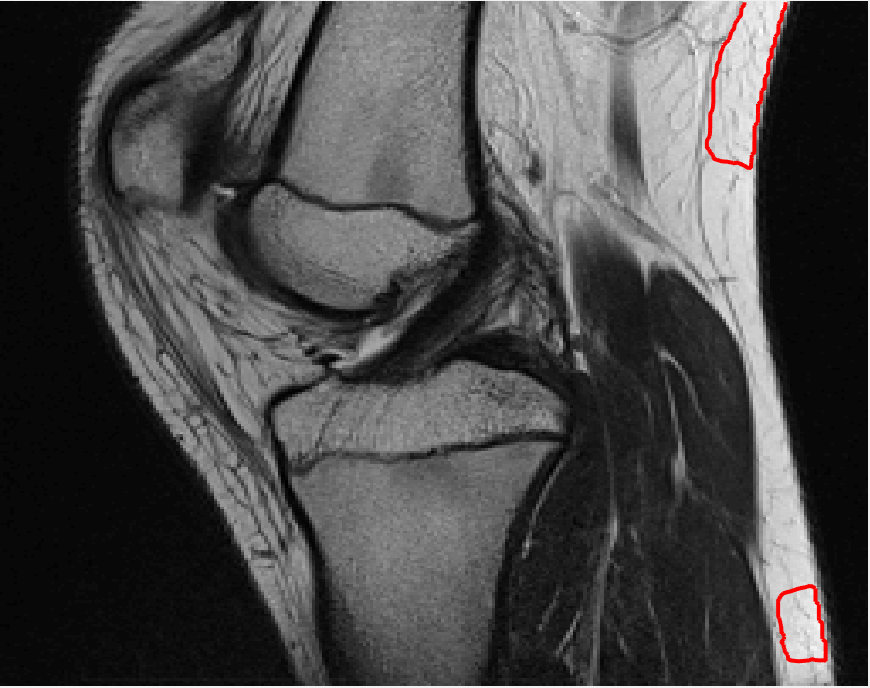

Four sets of test results are shown below. In Test 1 we compare models M1 – M6 to the proposed model M7 for two images which are hard to segment. The first is a CT scan from which we would like to segment the lower portion of the heart, the second is an MRI scan of a knee and we would like to segment the top of the Tibia. See Figure 9 for the test images and the marker sets used in the experiments. In Test 2 we will review the sensitivity of the proposed model to the main parameters. In Test 3 we will give several results achieved by the model using marker and anti-marker sets. In Test 4 we show the initialisation independence and marker independence of the Geodesic Model on real images.

Refer to captionRefer to captionRefer to captionRefer to caption

(i)                                 (ii)                                 (iii)                                 (iv)

Figure 9: Test 1 setting: (i) Image 1;  (ii) Image 1 with marker and anti-marker set shown in green and pink respectively;  (iii) Test Image 2; (iv) Image 2 with marker set shown.

Refer to caption

(a) M1 (Left to right:) Test Image 1 with markers (red) and anti-markers (blue), foreground segmentation and background segmentation (we used published software, no parameter choice required).

(b) M2 λ=1𝜆1\lambda=1, γ=10𝛾10\gamma=10.

(c) M3 λ=5𝜆5\lambda=5, θ=3𝜃3\theta=3.

(d) M4 λ=1/4𝜆14\lambda=1/4.

(e) M5 λ=5,γ=3,θ=110formulae-sequence𝜆5formulae-sequence𝛾3𝜃110\lambda=5,\gamma=3,\theta=\frac{1}{10}.

(f) M6 λ=15,θ=3formulae-sequence𝜆15𝜃3\lambda=15,\theta=3.

(g) M7 λ=10,θ=1formulae-sequence𝜆10𝜃1\lambda=10,\theta=1.

Figure 10: Visual comparison of M1 – M7 results for Test Image 1. M1 segmented part of the object, M2 – M4 failed to segment the object, M5 gave a reasonable result (though not accurate) and, M6 and M7 correctly segmented the object.